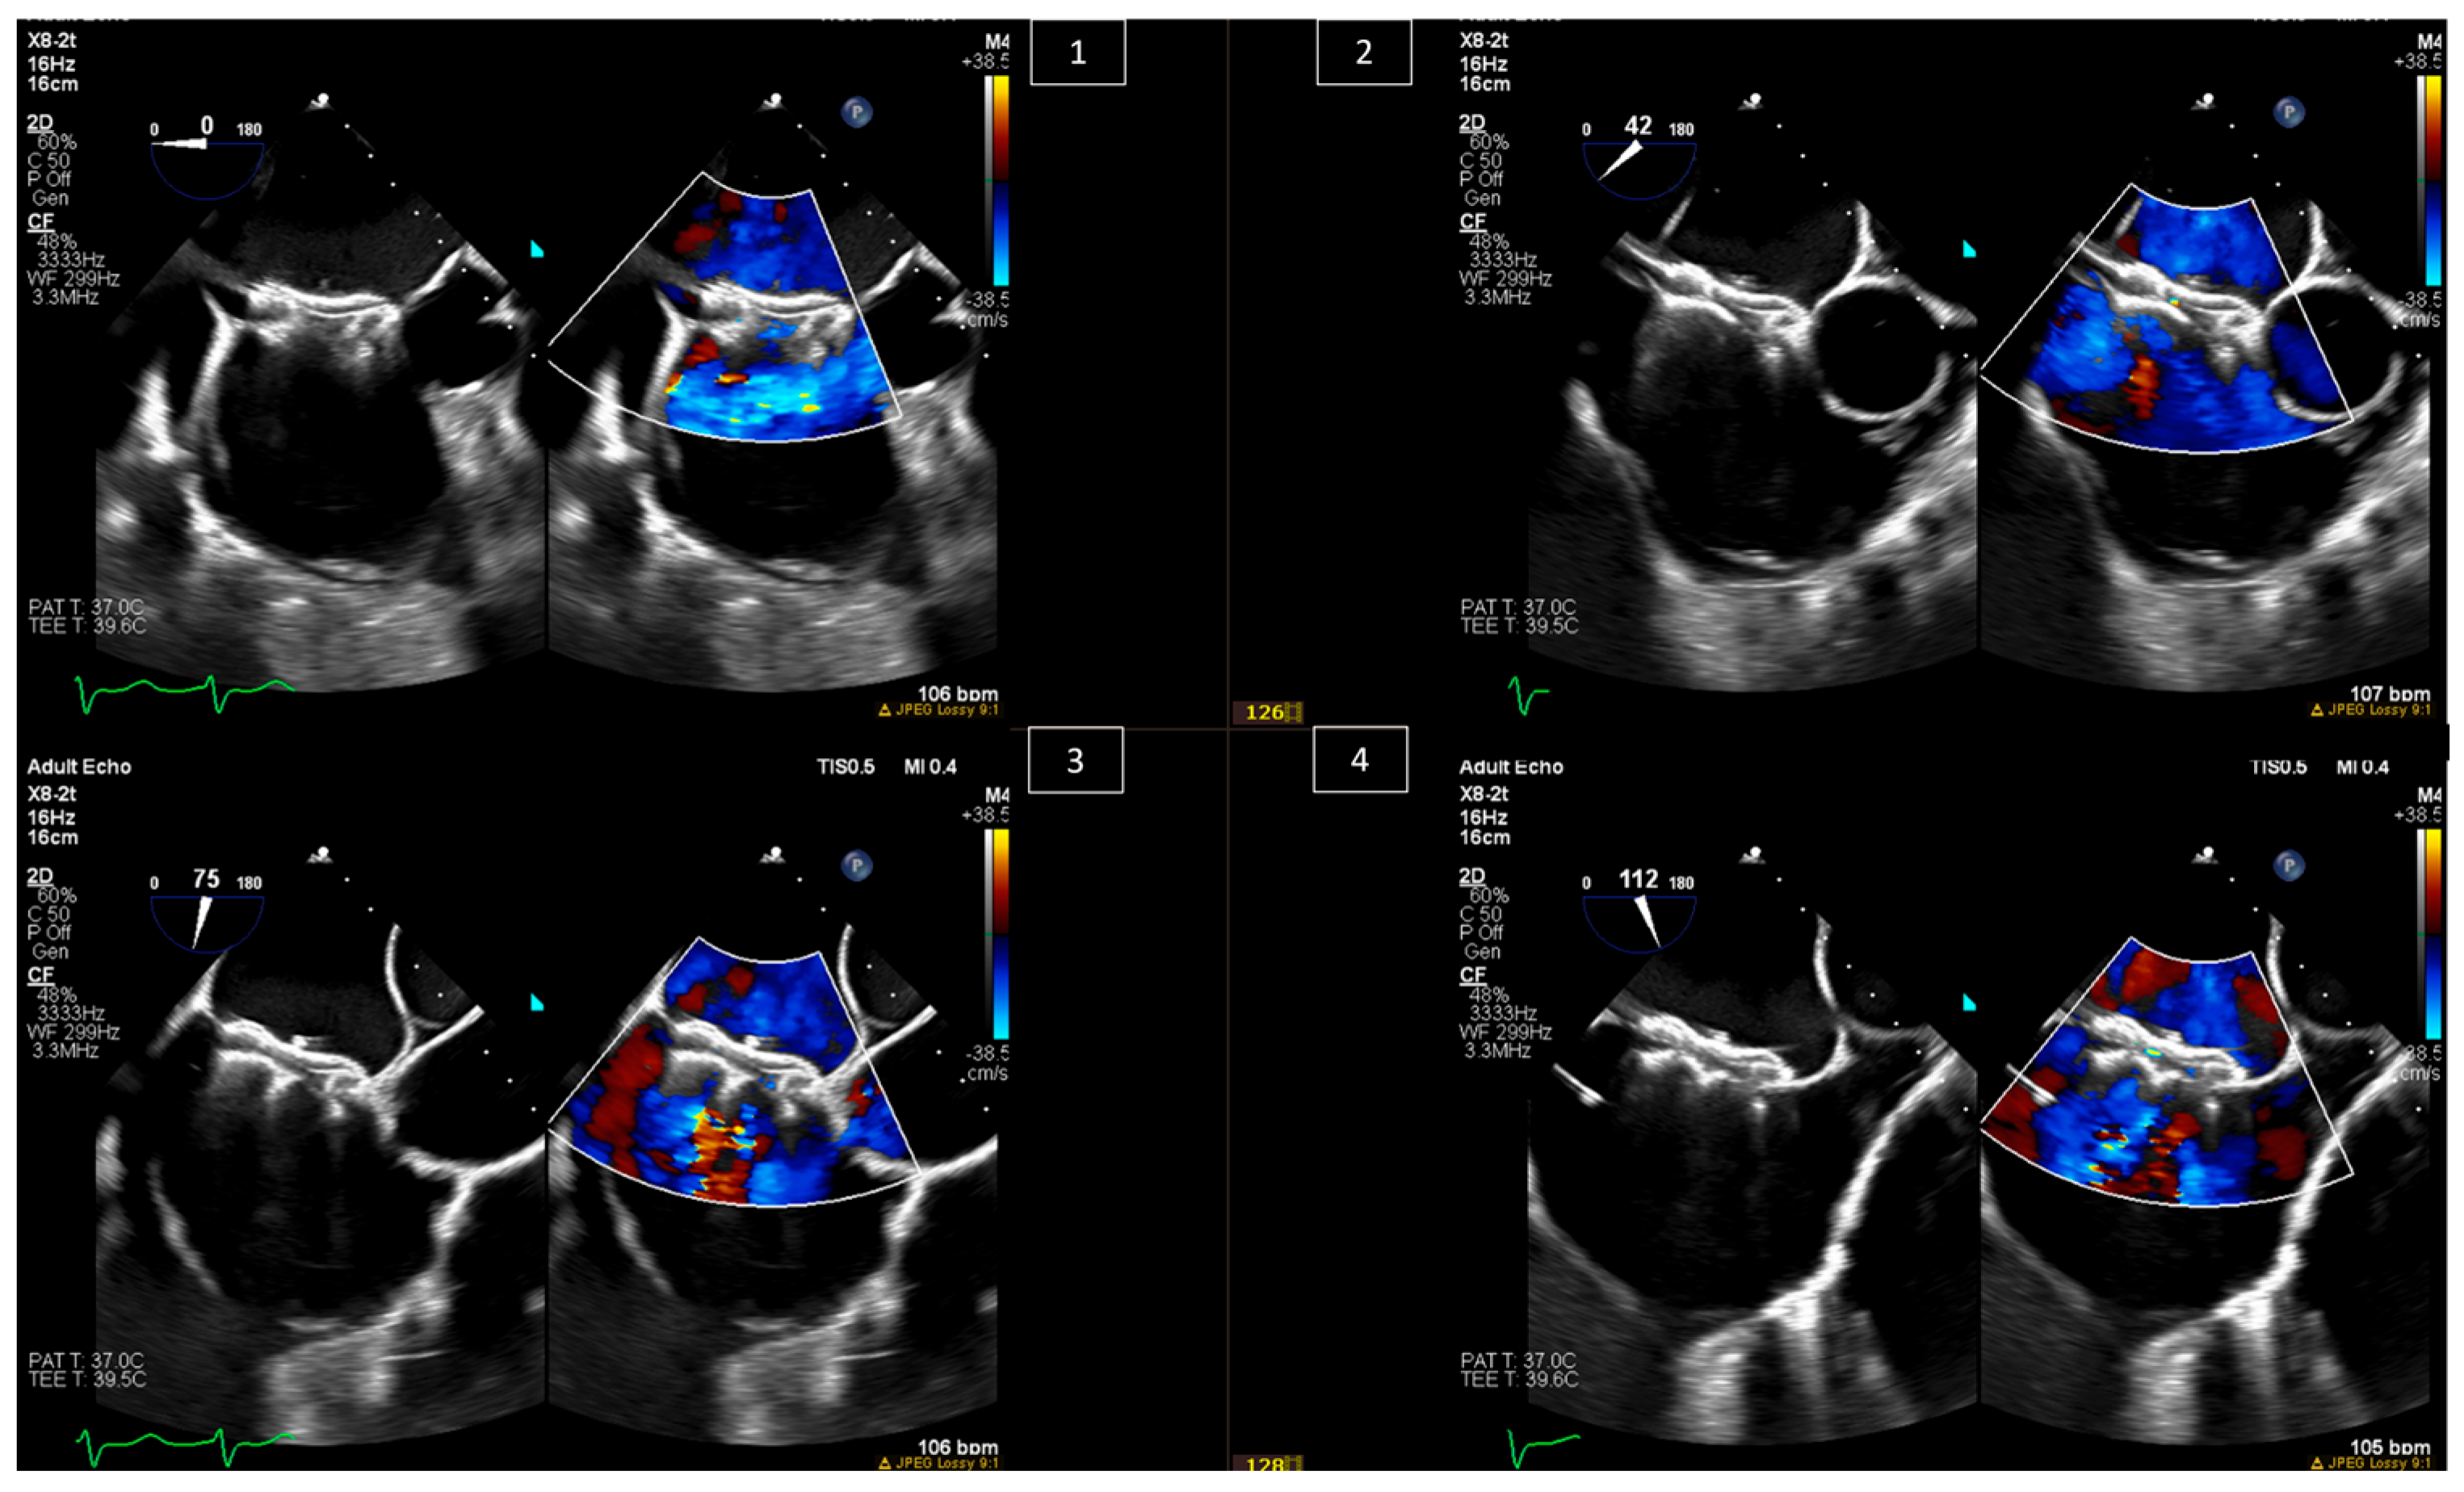

6. Baffle Complications in Atrial Switch Operations

7. Interventions in Fontan Circulation